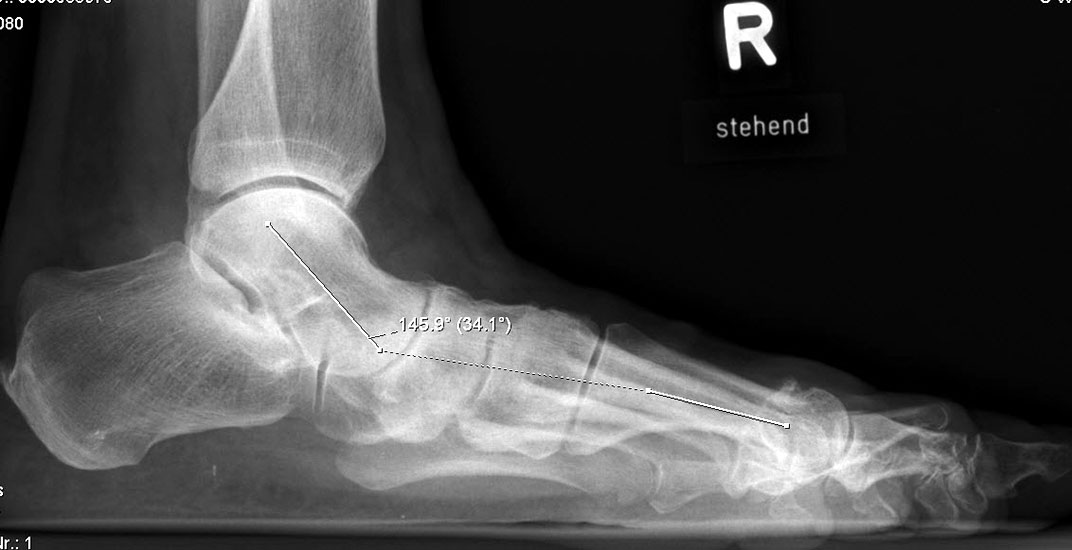

Auf der seitlichen, stehenden Aufnahme des Fußes wird ebenfalls der laterale Talo-Metatarsale I Winkel (Abb. 6 d) gemessen und so das kollabierte mediale Längsgewölbe dokumentiert. Auch hier gilt ein Talo-Metatarsale I Winkel von > 5° (nach plantar konvex) als pathologisch 21. Der Kollaps findet dabei meist im Talonaviculargelenk, seltener in der Naviculocuneiform-Gelenkreihe statt. Instabilität und Arthrose im 1. TMT sollten ausgeschlossen oder bei der Operationsplanung mit einbezogen werden. Weitere wichtige radiologische Messungen zur Beurteilung der Planovalgus-Statik und Progression der Deformität sind der laterale talo-calcaneare Winkel (Abb. 6 e) und der Abstand des Os cuneiforme-Unterrandes zum Untergrund (Abb. 6 f, Cuneiform height, 22. Eine anteriore Translation des Talus auf dem Kalkaneus findet man sowohl auf der ap, als auch auf der seitlichen Aufnahme des Fuβes mit Aufhebung der Cima-Linie.